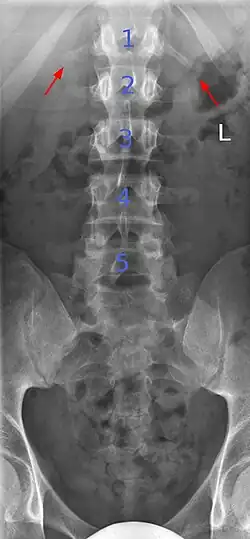

Butterfly vertebrae

Butterfly vertebrae have a sagittal cleft through the body of the vertebrae and a funnel shape at the ends. This gives the appearance of a butterfly on an x-ray. It is caused by persistence of the notochord (which usually only remains as the center of the intervertebral disc) during vertebrae formation. There are usually no symptoms. There are also coronal clefts mainly in skeletal dysplasias such as chondrodysplasia punctata. In dogs, butterfly vertebrae occur most often in Bulldogs, Pugs, and Boston Terriers.[10]